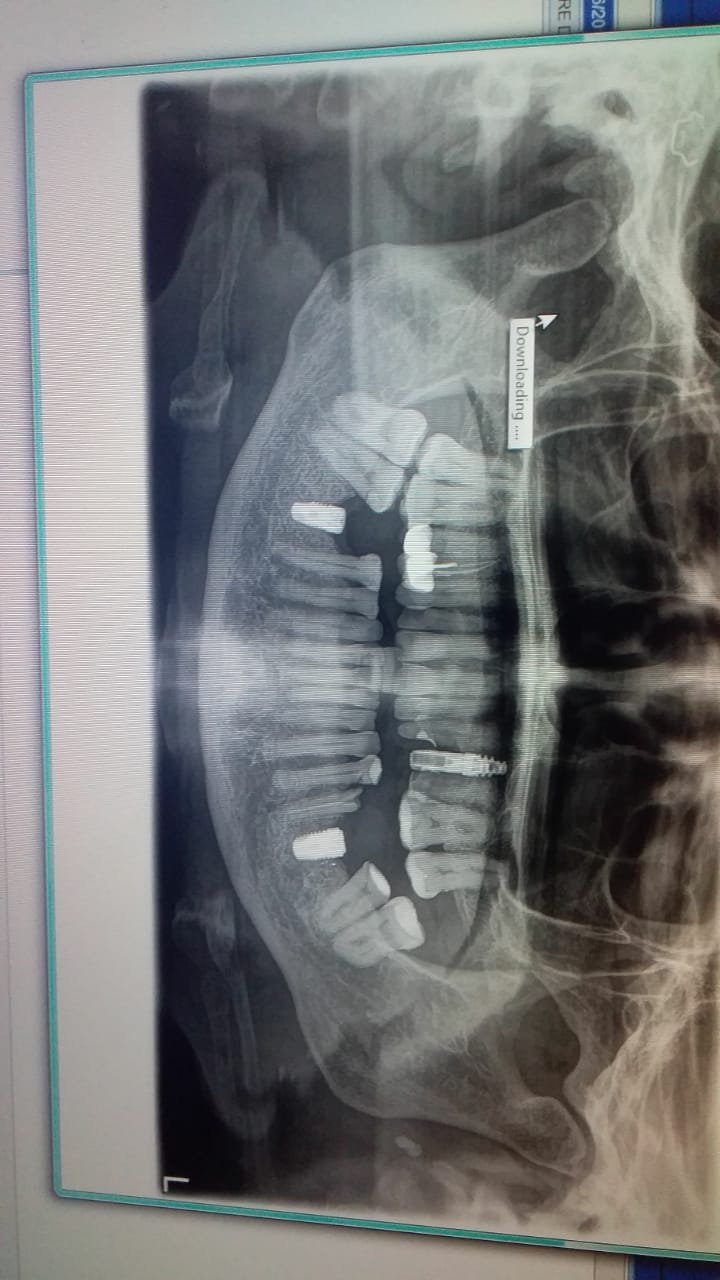

necesito saber la marca y medida si es posible de esos cuatro implantes inferiores muchas gracias